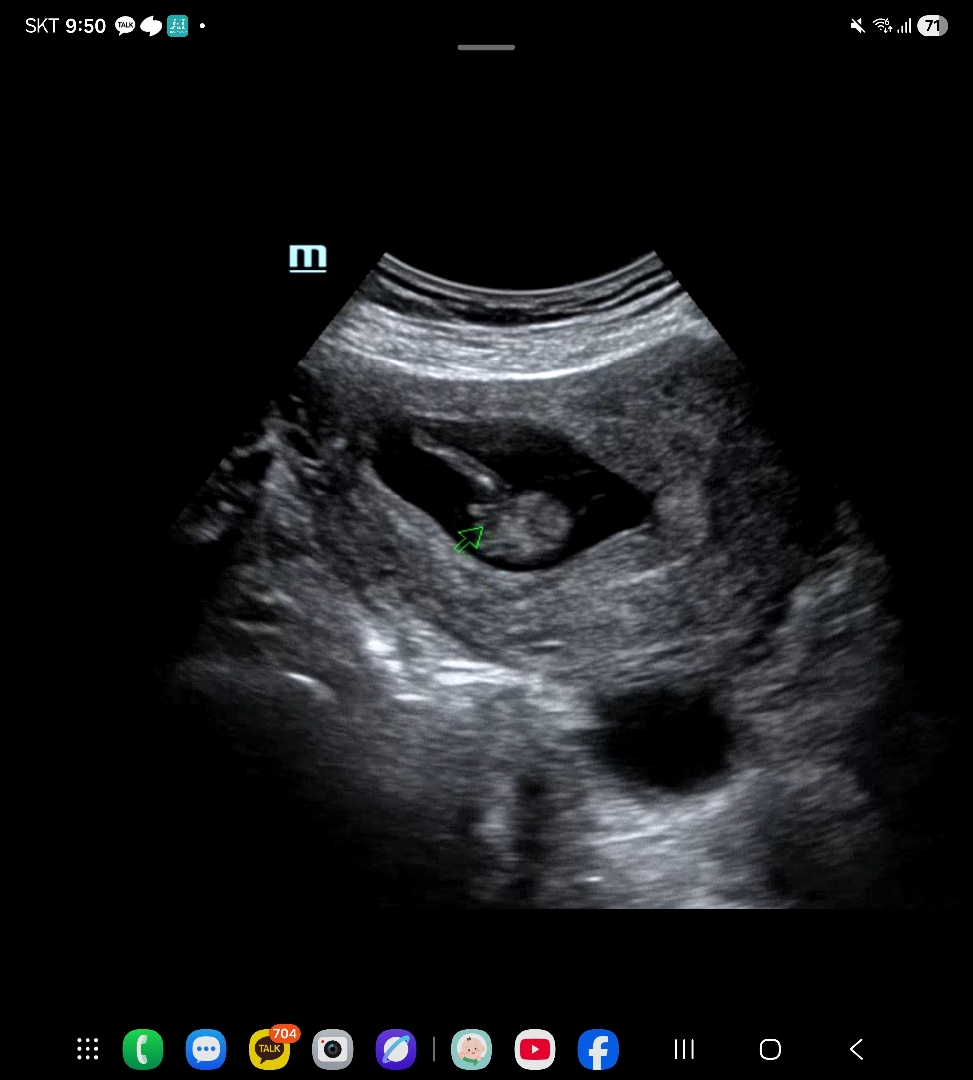

병원에서는 아들같다고 하시는데..

이번에 12주차가 됬는데 병원에서는 아들같다고 하시는데 선생님들 생각은 어떠실까요..